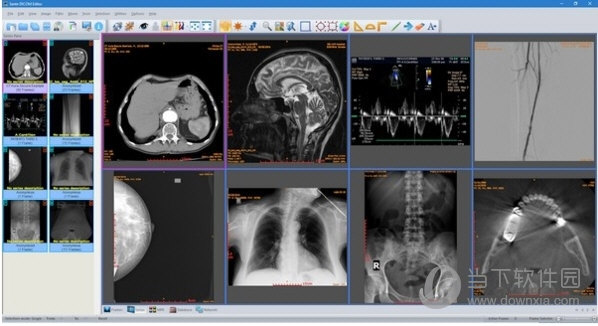

(the number of stored patients/studies depends on disk size only)Ĭommand line switches for integration with PACS servers (learn more.) It can be used as a mini PACS server as well PACS client that supports all the DICOM network services (C-FIND SCU/SCP, C-MOVE SCU/SCP, C-STORE SCU/SCP, C-GET SCU/SCP, C-ECHO SCU/SCP) Powerful DICOM workstation, viewer and editorįree updates and free technical support for product's life Among others, it lets the user to edit and modify DICOM files, to add and remove attributes, and even edit and modify sequence attributes. Sante DICOM Editor is the industry-leading post processing application for DICOM file editing, conversion and handling, it is used by almost all the large corporations and medical equipment manufacturers, and it is the DICOM editor of choice of the greatest universities and hospitals of the world. It is a unique program with unique capabilities, designed and developed in-house by us, from the ground up, with the most advanced programming tools and it is the result of research and development on DICOM imaging of the last two decades.

Sante DICOM Editor is not a "yet another DICOM viewer" constructed with freely available libraries such as dcmtk, itk and vtk, like hundreds of other DICOM viewers which differ from each other only in the appearance, menus, panels and dialog boxes. Sante DICOM Editor is a professional DICOM editor, viewer, anonymizer, converter, dicomizer, PACS client, mini PACS server, patient CD/DVD burner (with viewer) and much more.